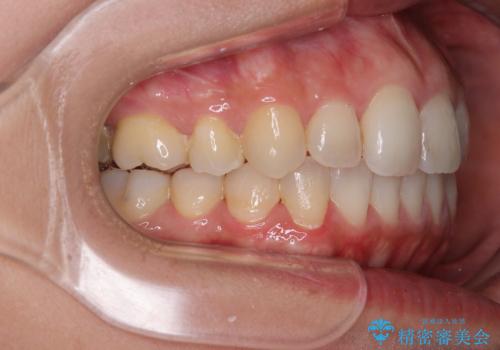

前歯のデコボコを改善 インビザラインの矯正治療

- 前歯のデコボコを治したいとのことで来院された患者様です。

上下顎ともに歯列全体の後方移動とIPR(歯と歯の間を削る)によってデコボコが解消するように設計し、インビザラインにより治療を行うこととしました。

下顎前歯は後戻りを起こしやすいため、舌側を細いワイヤーで固定し、マウスピース型リテーナーで保定を行うこととしました。